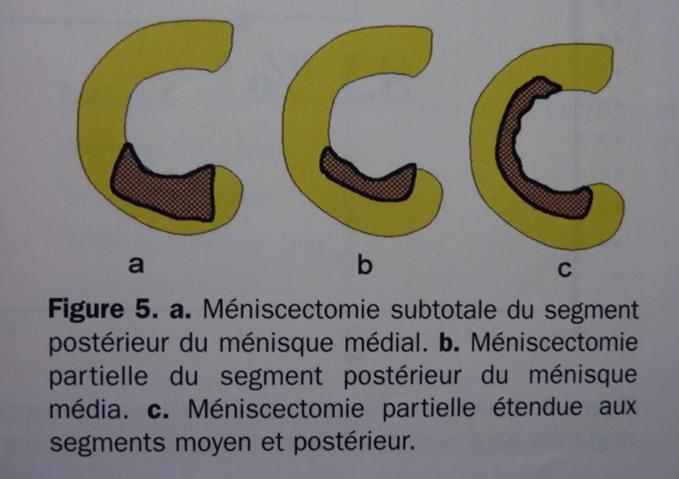

Par 2 mini incisions de chaque côté du tendon rotulien, on introduit dans l'articulation un arthroscope et des pinces emporte pièces appelées pinces basket, qui permettent une résection économique de la lésion. En fonction de l’importance de la lésion, la méniscectomie peut être partielle ou étendue, segmentaire ou sur plusieurs segments (Figure 7).

Figure 7: types de méniscectomies